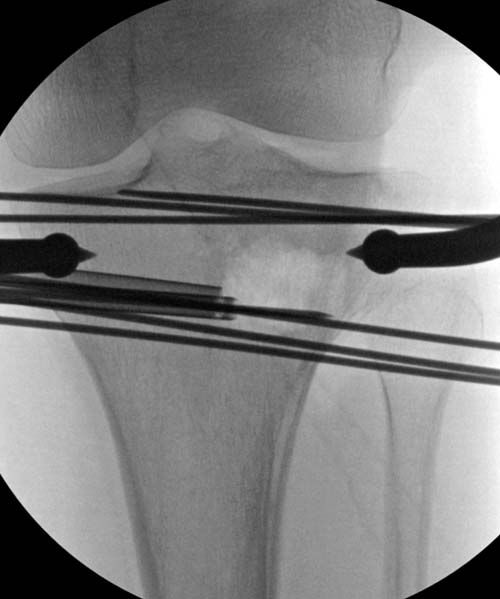

Для лечения некоторых видов центральной импрессии (Schatzker III) можно применить методику Balloon tibioplasty, которая позволяет приподнять сустав без дополнительных доступов. Для информации здесь недавний пример, дефект заполнен жидкой формой композитного материала PRO-DENSE: http://www.wmt.com/prodense/product_overview.asp